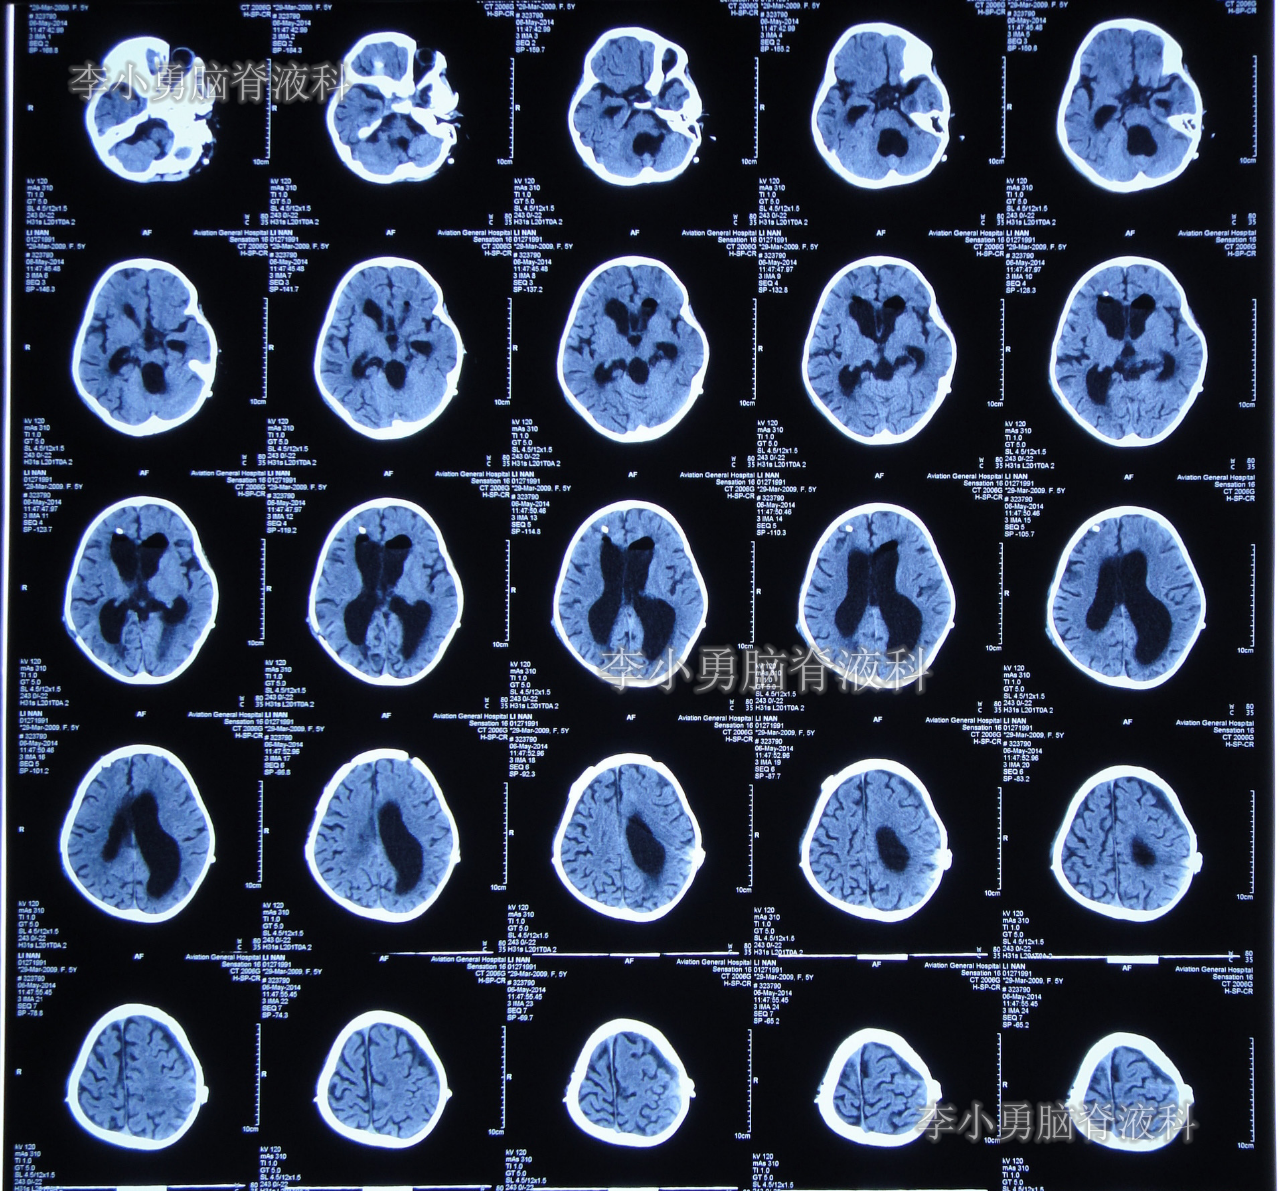

当天头颅CT示第四脑室包括在内的脑室系统全部显著扩张的表现(图-5)。

图-5:2014年3月17日入院时头颅CT

住院治疗第2天即2014年3月19日,复查头颅CT示第四脑室包括在内的脑室系统扩张程度虽均有所减轻,但第四脑室扩张程度仍严重(图-7)。

图-7:2014年3月19日头颅CT

住院治疗第28天即2014年4月14日,复查头颅CT示幕上脑室大小恢复到基本正常的状态,第四脑室再度显著缩小但仍稍大(图-11)。

图-11:2014年4月14日头颅CT

住院治疗第30天即2014年4月16日,查头颅CT示幕上和第四脑室均基本正常(图-13)。

图-13:2014年4月16日